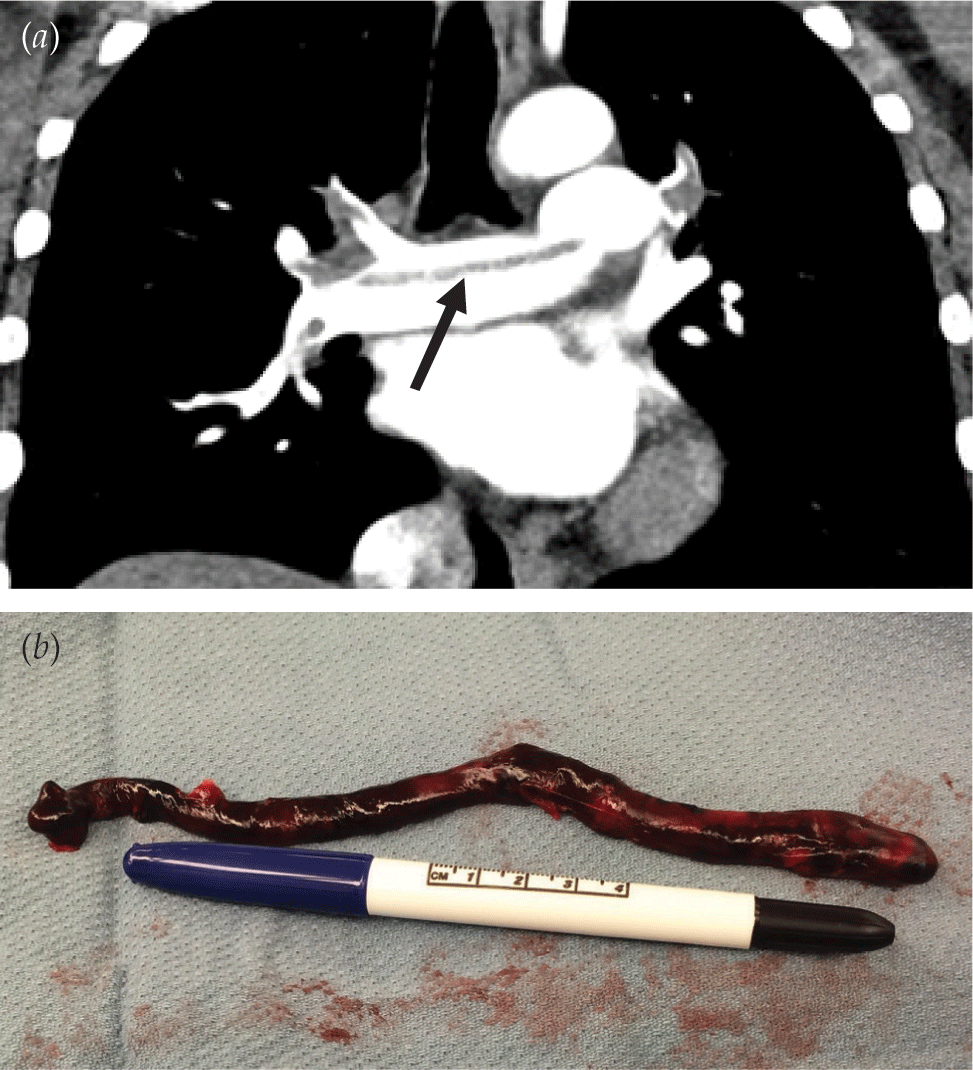

Risk Factors and Epidemiology of Pulmonary Embolism

- Despite advances in diagnosis and treatment, pulmonary embolism accounts for nearly 1% of all cardiovascular-related deaths in the United States annually.

- Pulmonary embolism is no longer considered an isolated event that requires short-term therapy but rather a chronic illness with long-term implications for patients.

- 2020 ASH and 2019 ESC/ERS practice guidelines for pulmonary embolism delineate the most recent diagnostic and therapeutic approaches.